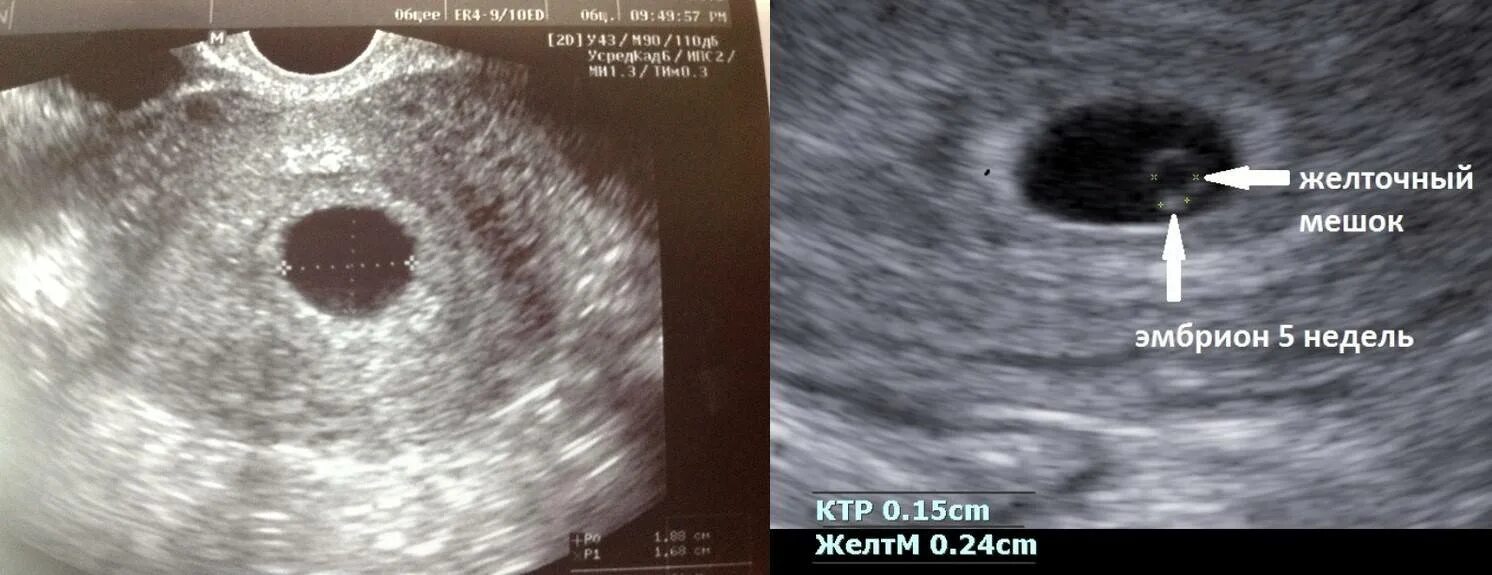

Симптомы замершей беременности второй триместр